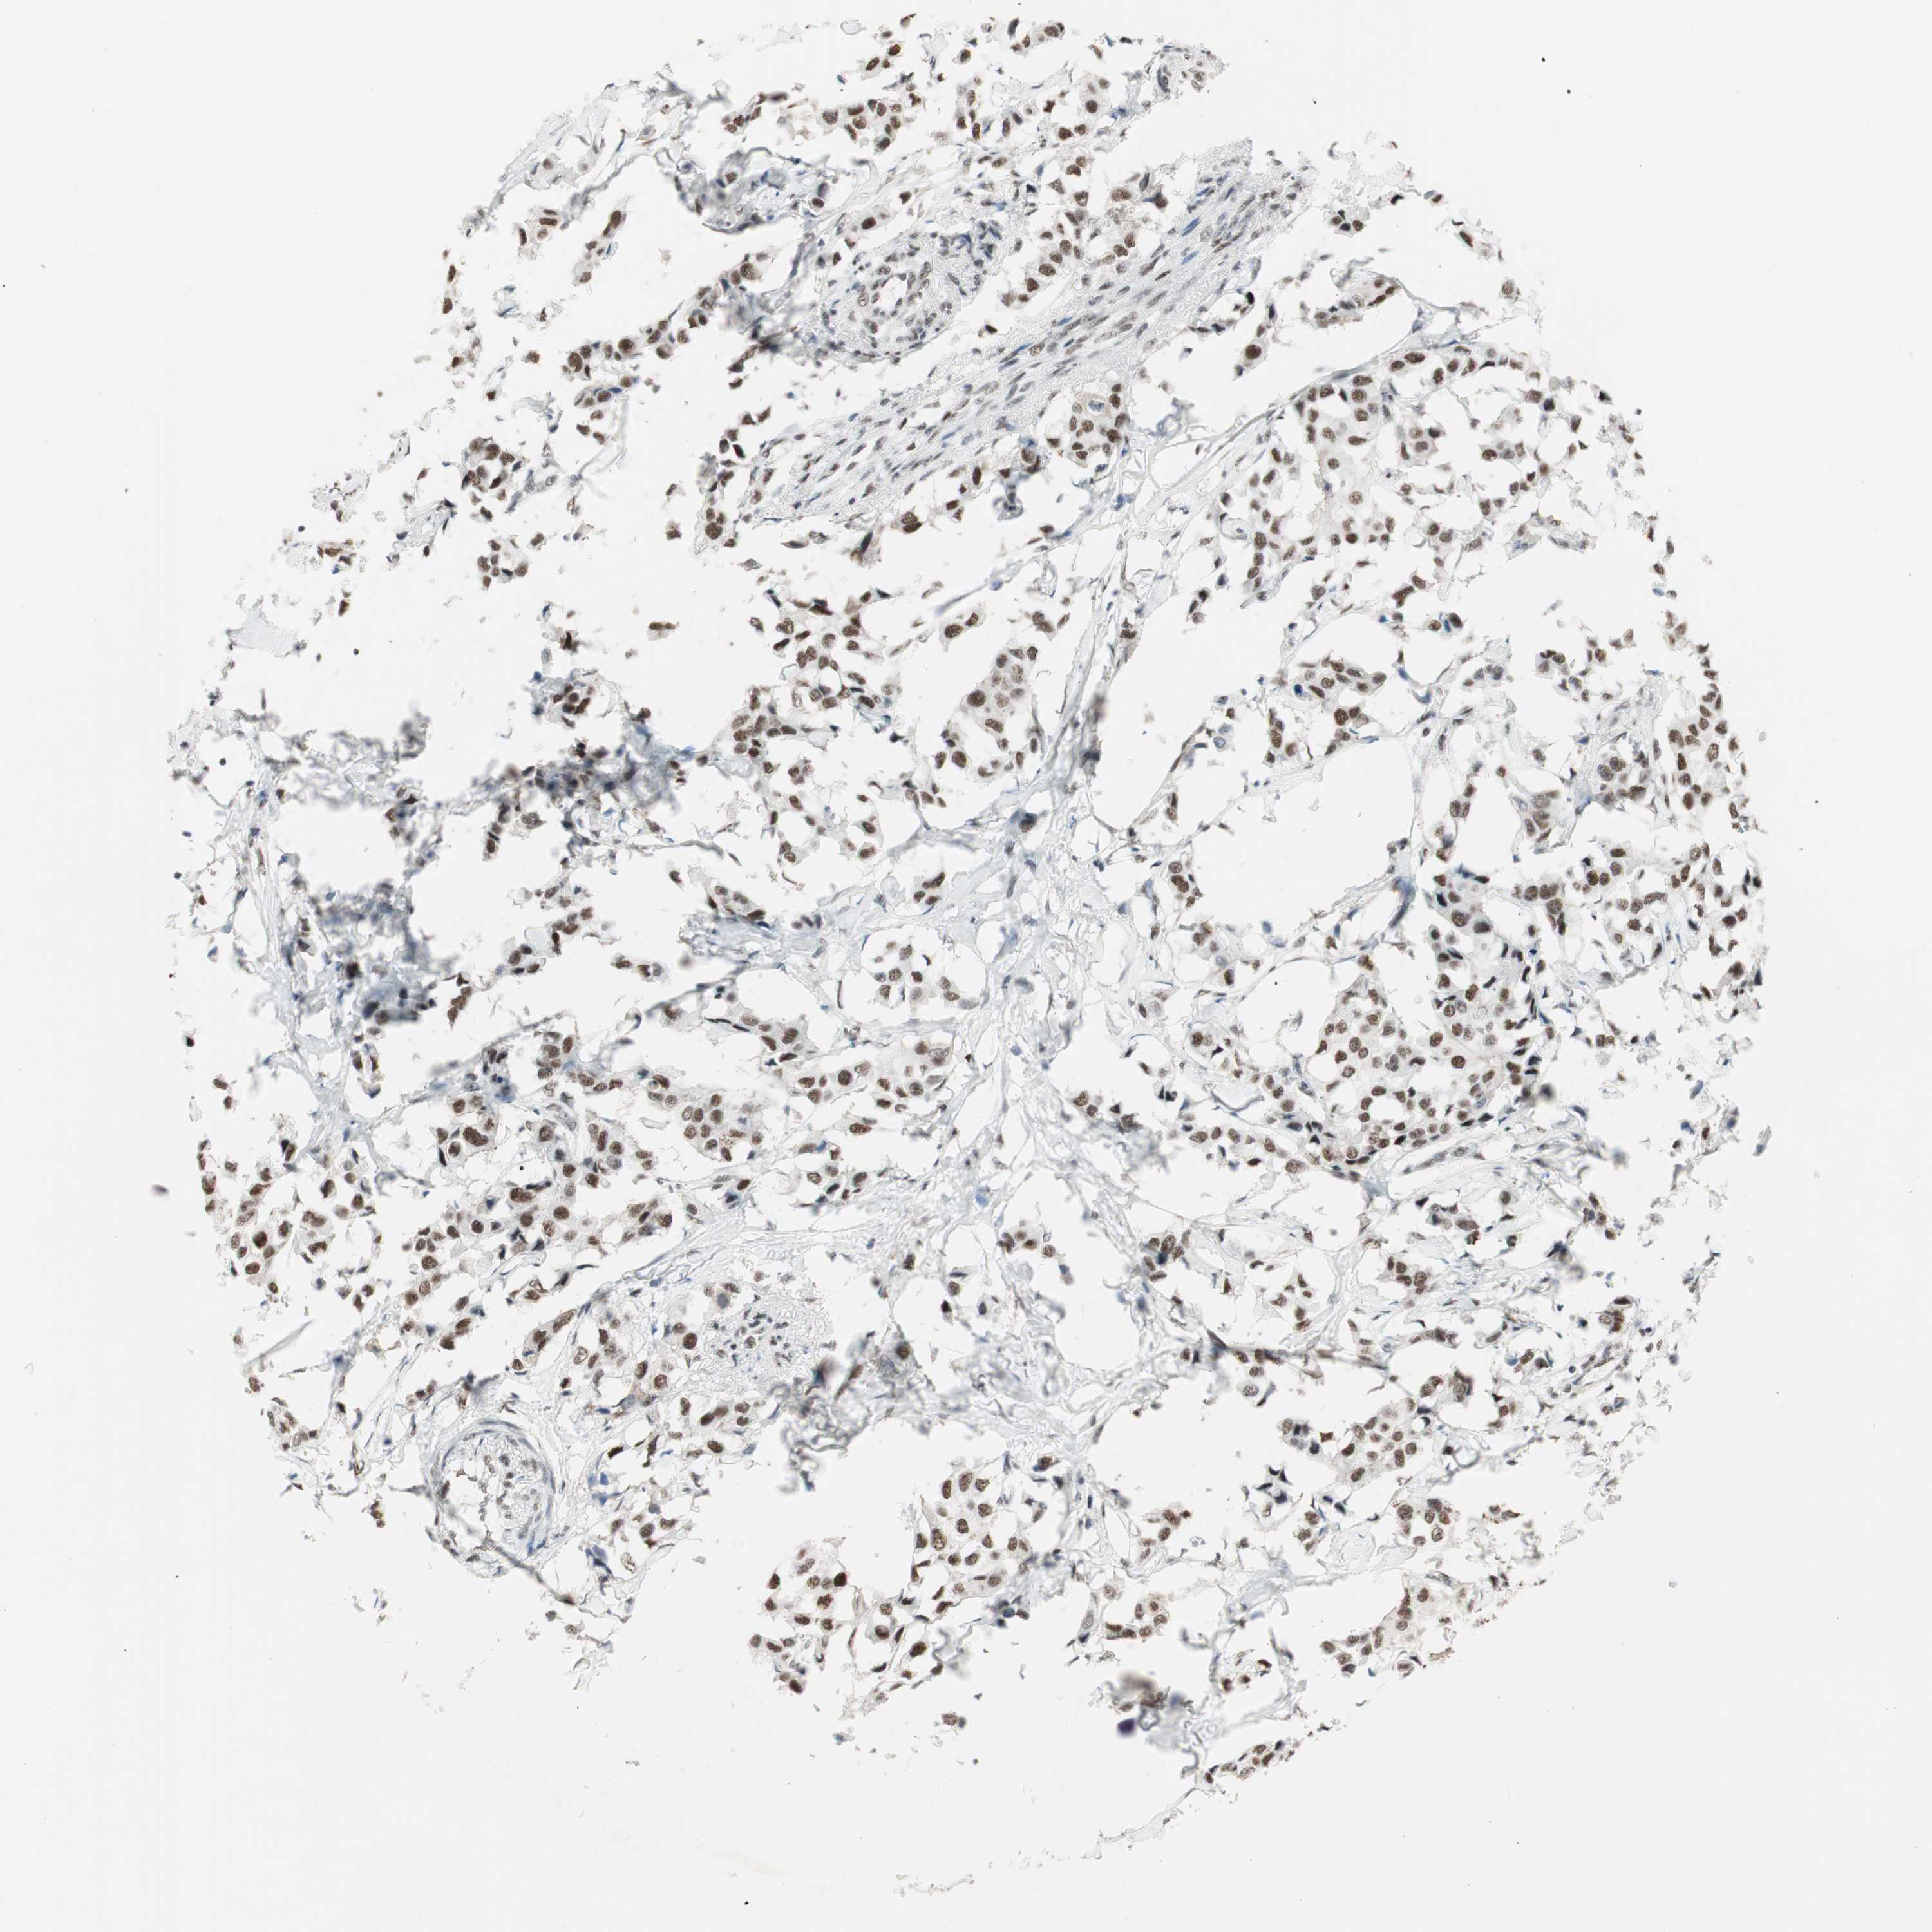

CANCER BREAST CANCER Show tissue menu

BRCA TCGA BRCA VALIDATION PROTEIN EXPRESSION